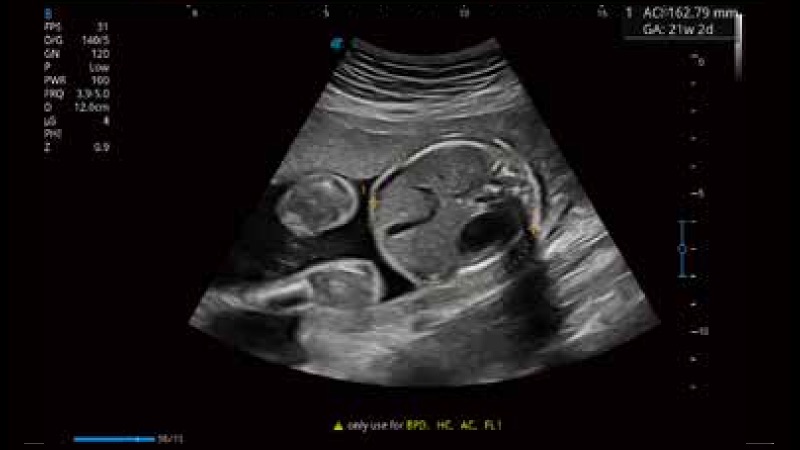

開立醫(yī)療通過不斷的技術(shù)創(chuàng)新,為大眾的生命健康提供持續(xù)關(guān)愛。P12 Plus采用全新一代超聲成像平臺,新平臺旨在將真實還原組織解剖結(jié)構(gòu)作為首要目標(biāo)。平臺采用全新集成化硬件模塊,搭載新一代芯片,系統(tǒng)性能得到大幅提升,為您的診斷提供了豐富的臨床信息。優(yōu)異的圖像表現(xiàn),豐富的探頭配置,全面的應(yīng)用功能,為您日常診斷提供了可靠的助手。

彩色多普勒超聲診斷系統(tǒng)